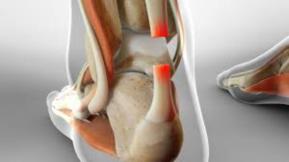

跟腱炎示意图1、跟腱炎发生的原因是什么?

跟腱炎的典型症状包括早晨起床时足后跟或脚踝的疼痛感,尤其是运动后次日更为明显。还可能观察到足后跟区域的增厚、肿胀,严重时可伴有骨质增生,影响足后跟的正常功能。

跟腱炎的不同位置跟腱炎通常发生在跟腱止点处或跟腱的中段。跟腱反复微创伤,会引起肌腱钙盐沉积,导致跟腱钙化。跟腱钙化后,可能出现不能长时间站立、走路疼痛、跟腱水肿等症状。